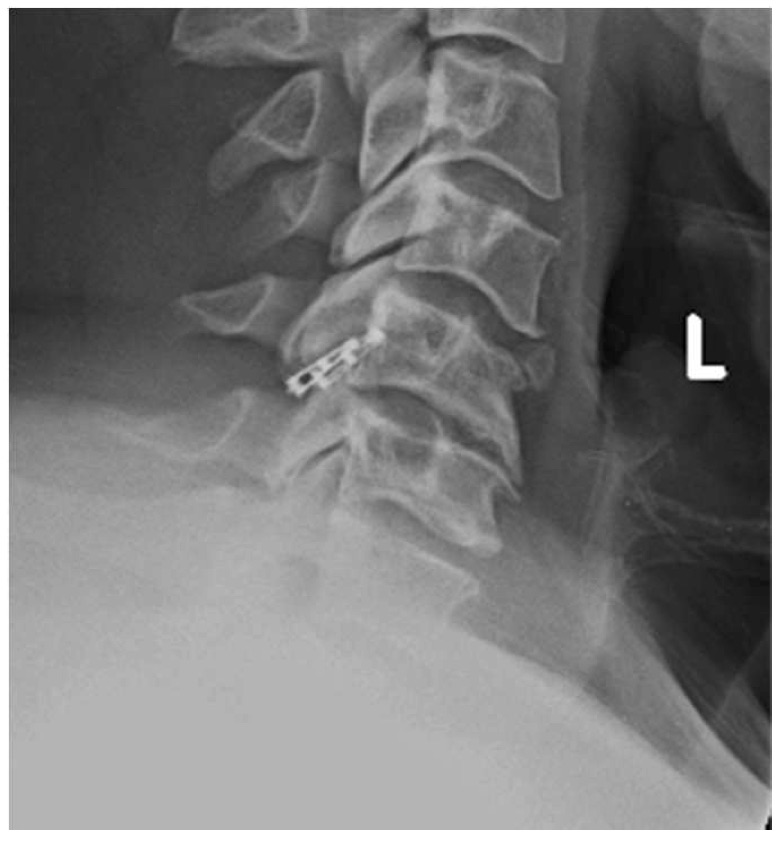

El sistema DTRAX® se compone de 2 cuñas de titanio que se introducen entre las facetas articulares cervicales para conseguir un aumento del espacio foraminal produciendo así la descompresión de la raíz o raíces nerviosas comprimidas a través de la distracción facetaria a la vez que produce una fijación estable de la articulación en el nivel implantado favoreciendo la fusión. Todo ello se realiza mediante un abordaje mínimamente invasivo gracias a un instrumental especialmente diseñado para ello.

DTRAX® está indicado para su uso en pacientes esqueléticamente maduros con patología degenerativa discal de la columna cervical (C3 a C7) con acompañamiento de radiculopatía y/o dolor facetario. La distracción facetaria que produce el DTRAX® hace que el espacio foraminal aumente aproximadamente en un 20% además de producir una estabilización de la articulación mayor en movimientos de rotación axial y movimientos laterales e igual en flexo- extensión si lo comparamos con la estabilización que produce una caja y una placa colocada mediante un abordaje anterior tradicional.